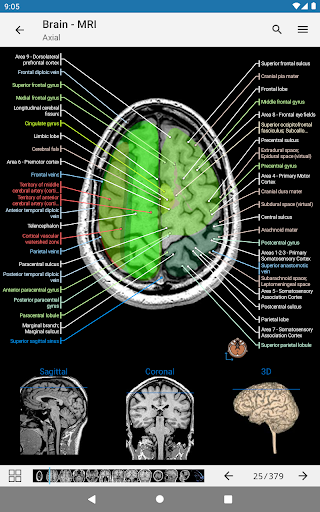

-A pictogram is now present on each image and represents the current orientation of the body

- “Filter by”, in the details view you can now filter the images containing the anatomical structure by modality

- The anatomic view now displays more labels